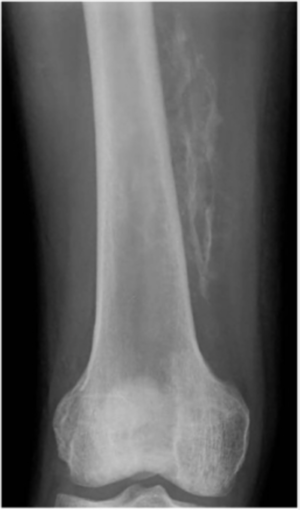

- Plain radiograph showing peripheral soft tissue calcifications

- Early radiographs may be non-diagnostic